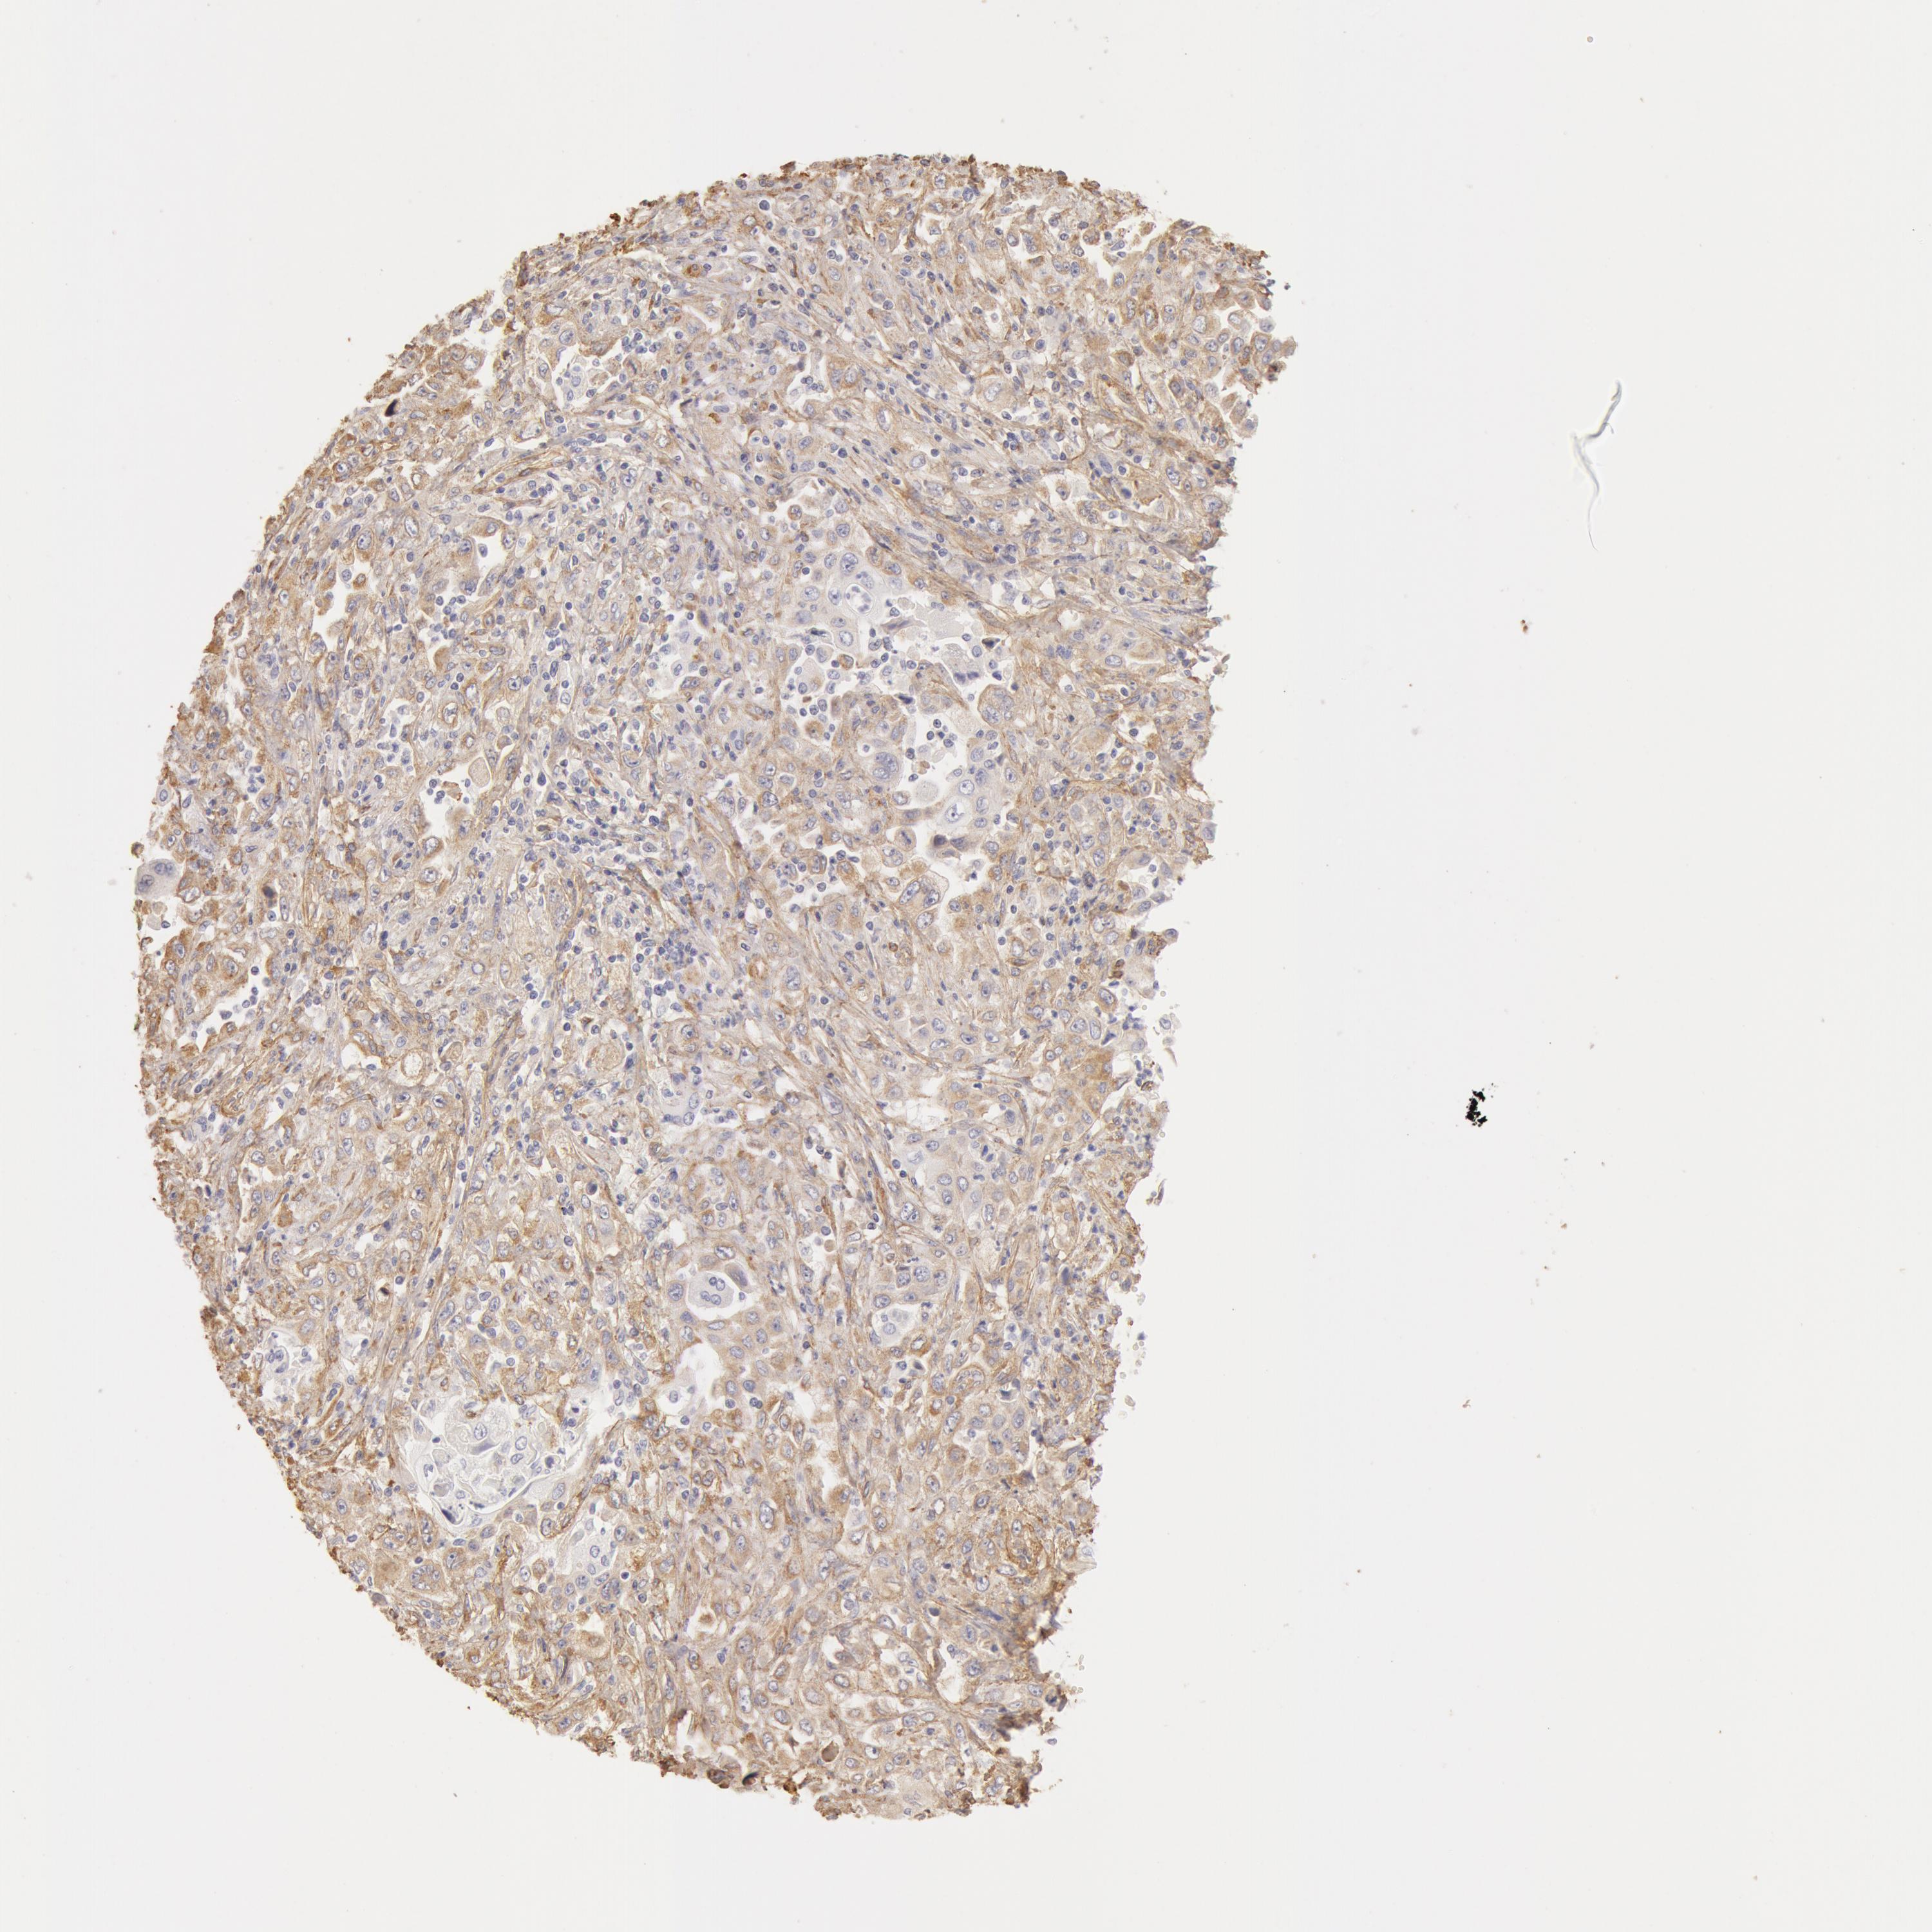

PANCREATIC CANCER - Protein expressioni

A mouse-over function shows sample information and annotation data. Click on an image to view it in a full screen mode. Samples can be filtered based on level of antibody staining by selecting one or several of the following categories: high, medium, low and not detected. The assay and annotation is described here.

Note that samples used for immunohistochemistry by the Human Protein Atlas do not correspond to samples in the TCGA dataset.

Antibody stainingi

Antibody staining in the annotated cell types in the current human tissue is reported as not detected, low, medium, or high, based on conventional immunohistochemistry profiling in selected tissues. This score is based on the combination of the staining intensity and fraction of stained cells.

Each image is clickable and will lead to virtual microscopy that enables deeper exploration of all samples and also displays staining intensity scores, fraction scores and subcellular localization as well as patient and tissue information for each sample.

Antibody CAB001695

Staining

High

Medium

Low

Not detected

Intensity

Strong

Moderate

Weak

Negative

Quantity

>75%

75%-25%

<25%

None

Location

Nuclear

Cytoplasmic/membranous

Cytoplasmic/membranous,nuclear

Adenocarcinoma, NOS